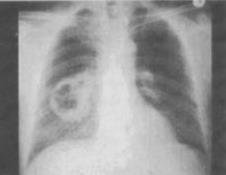

- 单项选择题 患者男,54岁,咳嗽,伴胸痛2周,午后有低热,胸片如图,最可能的诊断是()。

A、肺脓肿

B、结核空洞

C、韦格肉芽肿

D、肺癌

E、肺大疱

- D